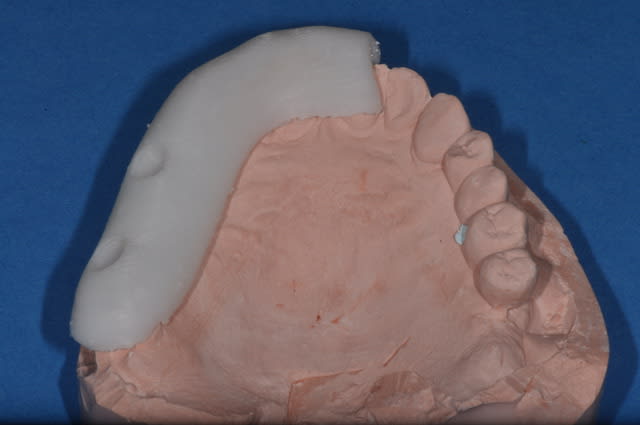

la planif. définitive du cas de la vidéo

et le premier guide à appui dentaire avec la technique de patrick

On devrait pouvoir se dispenser du guide radiologique, ce qui diminuerait les couts!!!!!!!!!!!!!!!

pas trop sexy ton guide !

Tu as de la résine translucide ou même transparente ?

tu as aussi besoin de puits pour l'eau de refroidissement...

sinon nonos v a cuire...